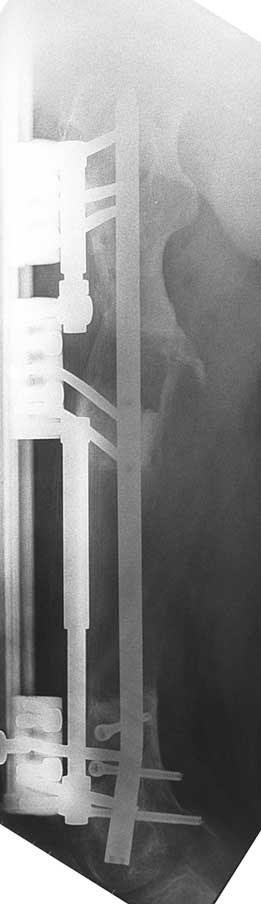

Appropriate radical debridement necessitates excision of all necrotic bone and soft tissues, and frequently causes instability at the involved extremity. The remaining bone and soft tissue defect has to be fixed and reconstructed. The distraction osteogenesis method of Ilizarov is used successfully for achievement of union, correction of the deformity, elimination of limb length inequality and reconstruction of segmental bone defects.

The duration of external fixation (external fixation index) depends on the amount of distraction required, and the extremity is prone to complications during this period. After the distraction phase is completed, the external fixator remains in place during the consolidation phase, which lasts twice as long as the distraction phase; but this period is hardly tolerated. If the external fixator is removed before sufficient consolidation is achieved, fractures, deformity and shortness will be the result. In our department, ‘lenghthening over nail’ method is used in order to decrease the external fixation index and increase patient comfort and activity level. In this method, the intramedullary nail is statically locked after the completion of the distraction phase, and external fixator is removed. The extremity is stabilized by the intramedullary nail during consolidation phase. In this way, complications due to long external fixation index or early removal of the external fixator are avoided.